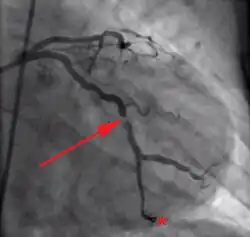

Hochgradige Verengung einer Koronararterie

Die instabile Angina pectoris ist die einfachste Form eines akuten Koronarsyndroms. Sie geht mit einem großen Herzinfarktrisiko einher. Kennzeichnend sind Änderungen in der Symptomatik, wie beispielsweise das erstmalige Auftreten von Angina-pectoris-Beschwerden, das Auftreten von Beschwerden in Ruhe oder die Zunahme der Anfallsdauer, Anfallshäufigkeit oder Schmerzintensität.[15] Als instabil werden auch Angina-pectoris-Beschwerden vor (Präinfarktangina oder Präinfarktsyndrom als Unterform der instabilen Angina)[16] sowie innerhalb von zwei Wochen nach einem Myokardinfarkt bezeichnet.[17] Typischerweise ist auch die Wirkung von Nitroglycerin herabgesetzt.[9]

Der instabilen AP liegt in der Regel eine koronare Gefäßerkrankung und Arteriosklerose zugrunde. In diesem Rahmen kommt es zu einem lokalen Einriss von arteriosklerotischen Plaques in Koronararterien. Dies führt zu einer mechanischen Teilverlegung sowie reflektorischen Verengung der Arterien durch Vasospasmus. Ein sich bildender Thrombus kann einen akuten Myokardinfarkt auslösen.[15] Die Angina decubitus (auch Angina nocturna[18]) ist eine Form der instabilen Angina pectoris mit insbesondere nachts im Liegen auftretenden thorakalen Schmerzen. Ursache hierfür ist die Überlastung der vorgeschädigten Herzmuskulatur bei vermehrtem venösen Blutrückstrom im Liegen.[19]